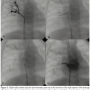

Patient 2. A 10-month-old infant was referred to our hospital with the diagnosis of bilateral pulmonary veins restenosis after surgical procedure with sutureless technique in the right-sided ostium and patch angioplasty on the left-sided ostium. During the surgical procedure, the surgeon left a small atrial septal defect. The patient presented clinically unstable with signs of supra-systemic pulmonary artery pressures at echocardiography and was referred for an attempt of percutaneous balloon dilatation of the pulmonary veins. At cardiac catheterization, right ventricular pressure was 120% of the systemic pressure. Selective angiography at the ostium of the right upper pulmonary veins clearly demonstrated stenosis that was dilated with 3 mm x 20 mm and 3.5 mm x 20 mm Hiryu balloon (Terumo) and post-dilated with 5 mm x 20 mm Quantum Maverick balloon (Boston Scientific) (Figure 5A). However, it was very difficult to cannulate the insertion of the medium and inferior lobe drainage due to an extreme angulation. After various attempts with usual catheters and guidewires, we used the Venture catheter to inject contrast and confirm the stenosis and then to cannulate with a 0.014" support guidewire. We then performed successful balloon dilatation with 3.5 mm x 20 mm Hiryu balloon (Terumo) and post-dilation with 5 mm x 20 mm Quantum Maverick balloon (Boston Scientific) (Figures 5B-5D). Using a 5 mm x 20 mm Quantum Maverick balloon, we performed dilatation of the obstructed ostium of the left-sided pulmonary veins. Procedure was uneventful and pressure in the right ventricle decreased to 60% of the systemic pressure. The patient was discharged 10 days later clinically well and with a stable result.